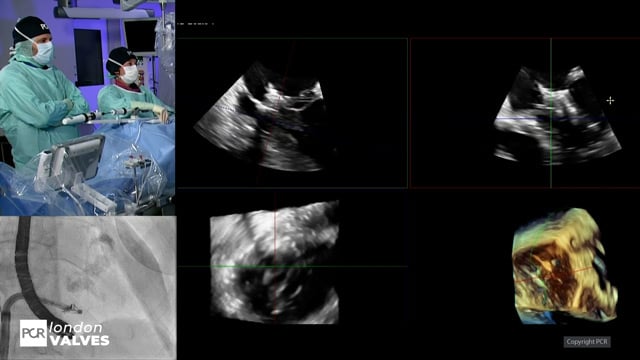

Innovation for transcatheter tricuspid interventions - LIVE case

24 Nov 2024 – From PCR London Valves 2024

Dive into the world of innovation for transcatheter tricuspid interventions. Discuss the remaining challenges associated with currently available options, capture the central role of imaging guidance, and understand the anatomical selection criteria for transcatheter tricuspid valve replacement. Experience a live case from St. Thomas' Hospital, London,...